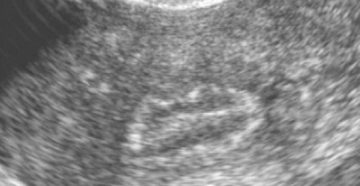

Кальцинаты в матке: причины образования, диагностика, лечение В медицинской практике кальцинаты определяют как отложения кальциевых…